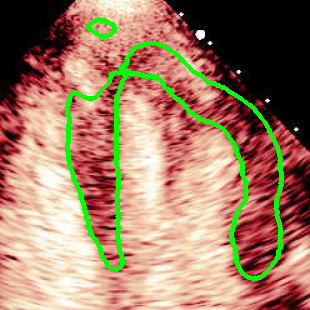

For variations caused by low quality images such as those of low resolution or significant artifacts, however, the unique ground truth may not be available. Take the myocardial segmentation task of Myocardial Contrast Echocardiography (MCE) as an example. An inter-observer experiment was conducted among five experienced cardiologists, and Fig. 1(a)(b) visualize the annotations of two images from three of these cardiologists. It can be seen that the labels by different cardiologists vary significantly, especially in locations where the intensity information of myocardium is very similar to the background. Table 1 shows the average Dice of the annotation of each cardiologist, using one of the others’ as the ground truth, over 180 images. We can observe that none of the Dice is above 0.9, some even under 0.8, confirming significant variations among the annotations. In this case, as the variations are caused by the image quality, even these cardiologists cannot tell which annotation is better than others, and a majority vote for ground truth would not make sense sometimes as can be seen in Fig. 1(c)(d). For this reason, we cannot obtain a unique ground truth in the evaluation process and the traditional metrics such as Dice and IoU cannot be used.